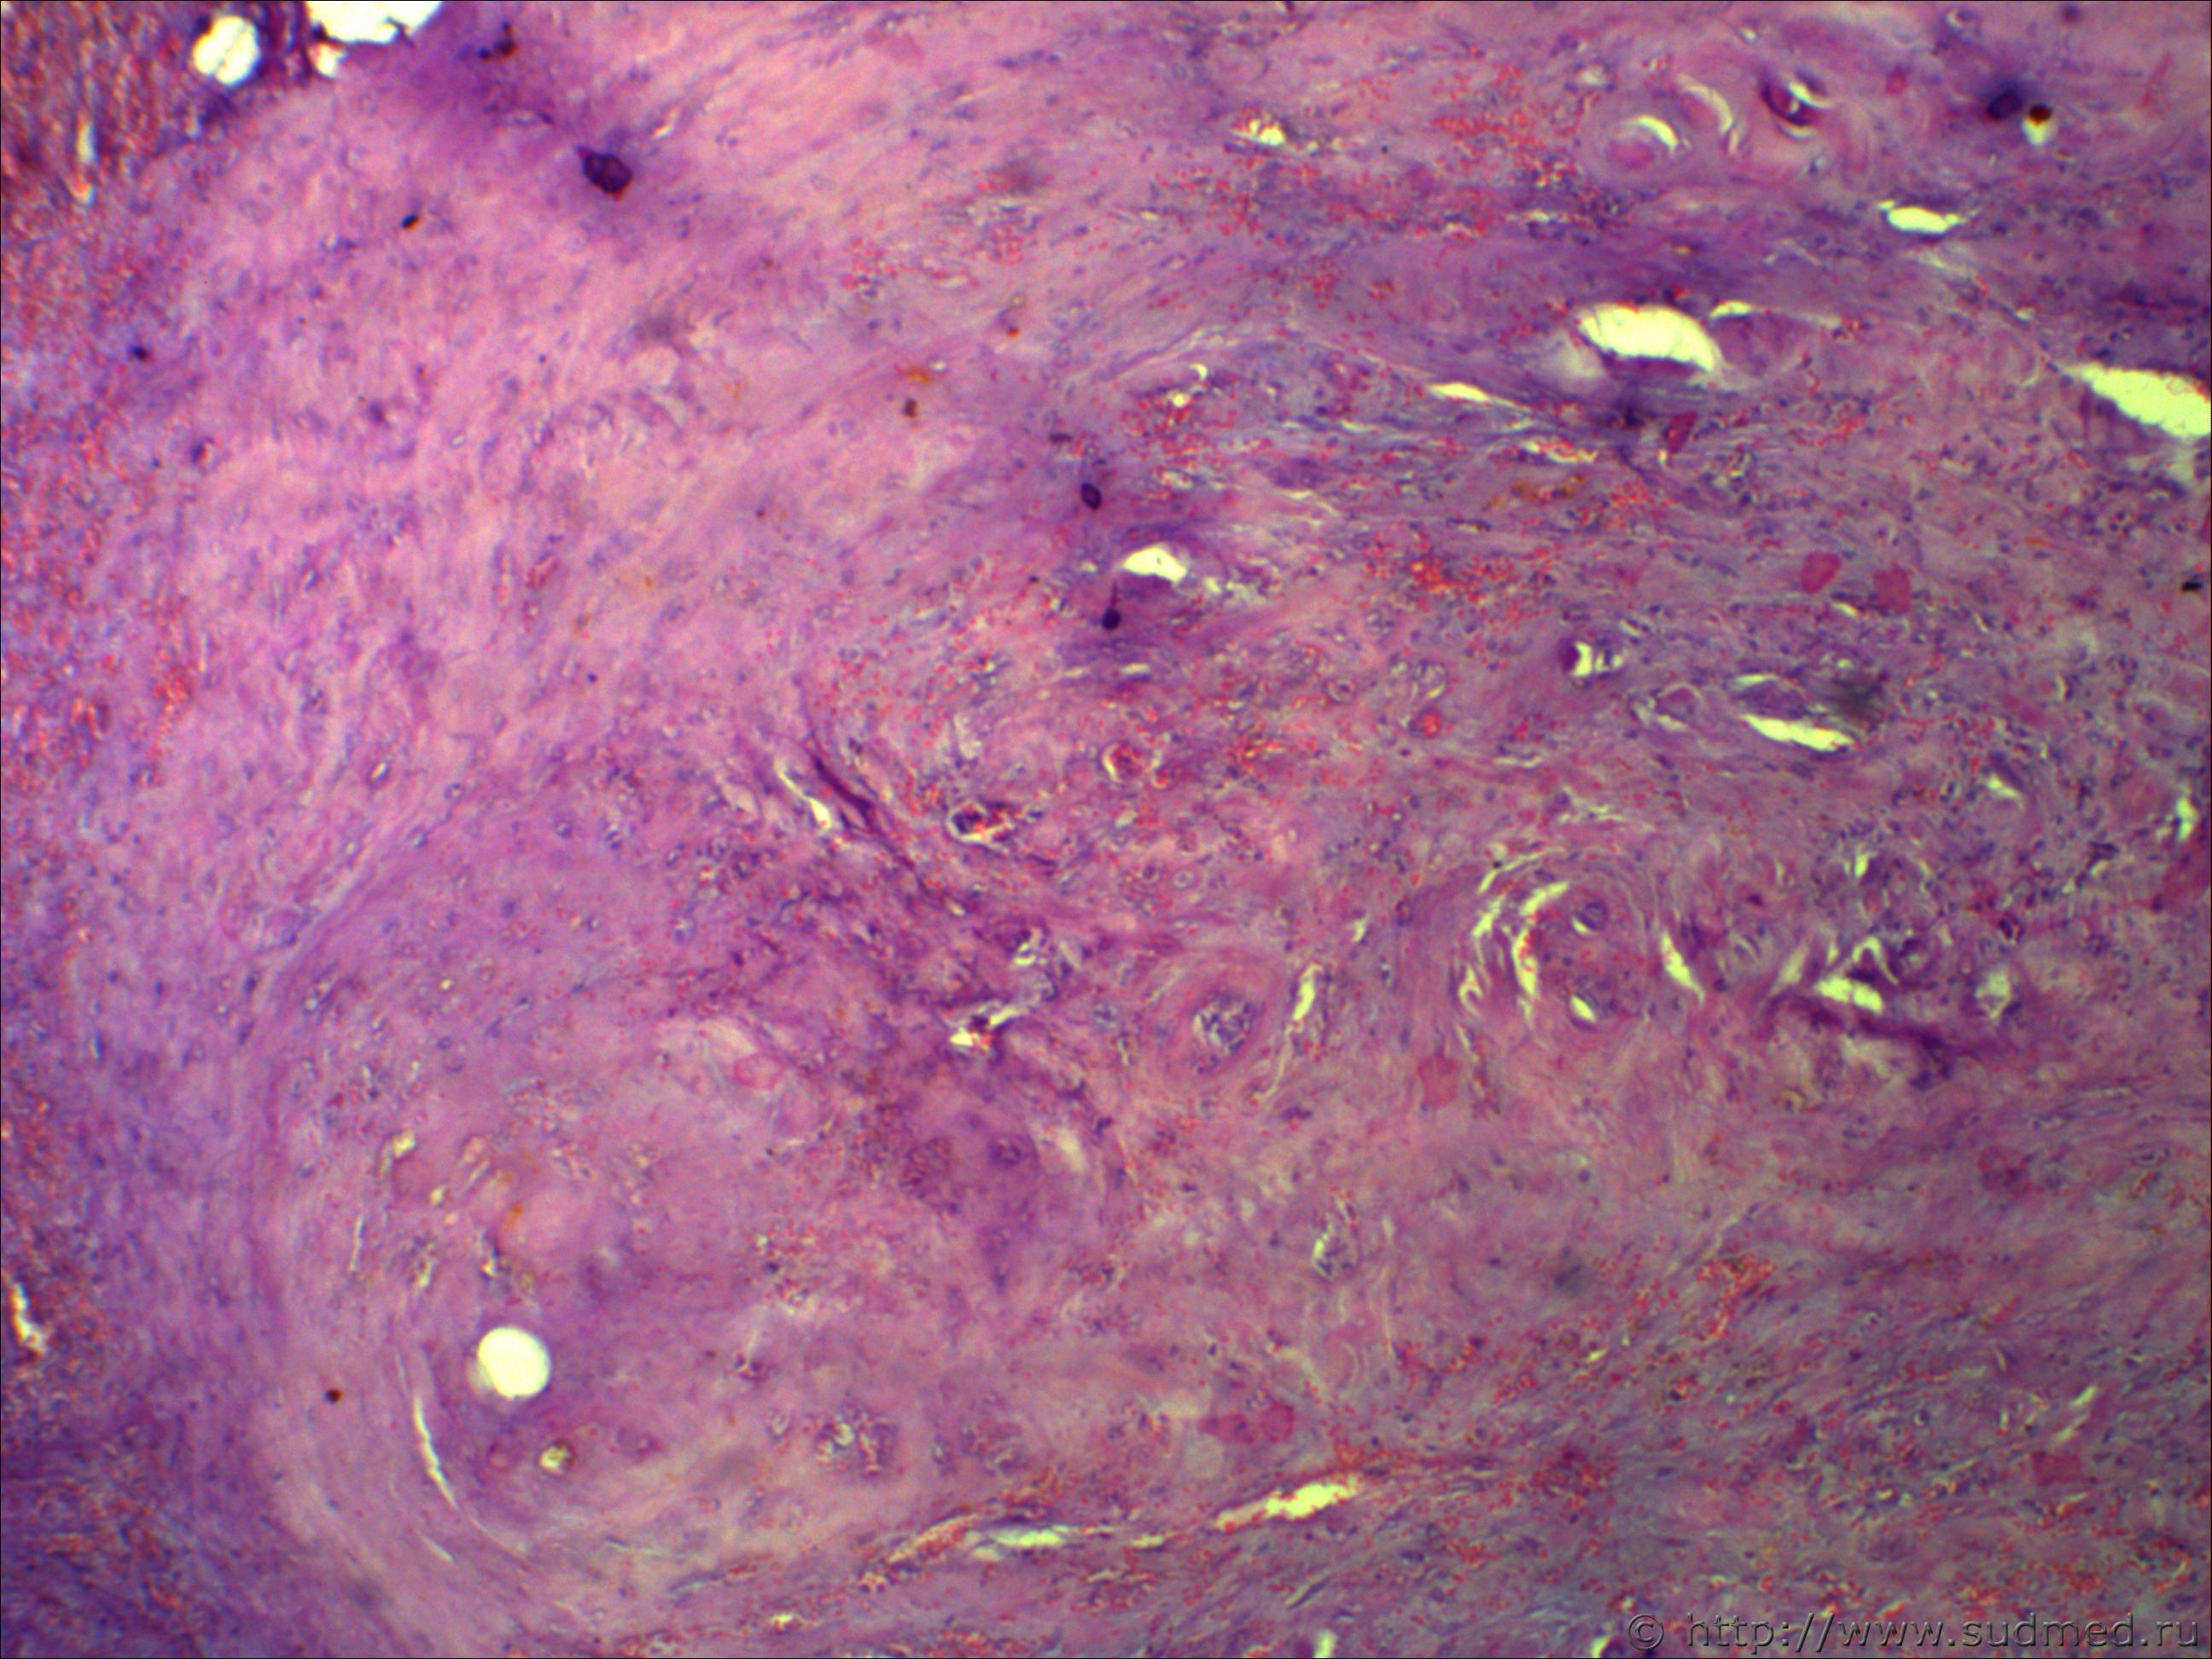

Н/О округлой формы четких границ, на теле фибринозно-кистозной структуру 5*7см!

Похоже на ангиофиброму.

Не фибринозно, а фиброзно-кистозная структура. Пока об ангиофиброматозе нужно думать, требует дальнейшей дифференциации.Срезы толстые. Наблюдается эндотелиальная пролиферация...

Ничего такого не понял, вижу:

- новообразование сосудов. полнокровие очаговое

- очаговый гиалиноз

- смешанную фиброму (типическую)... да их столько с примесью кистозного элемента

- митозов не вижу